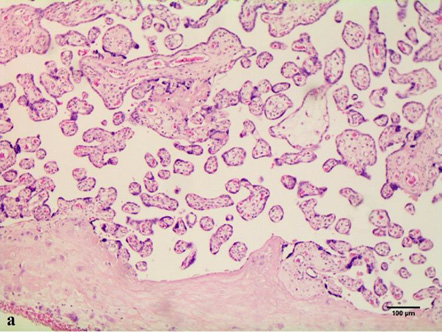

In cases of maternal vascular malperfusion, villous hypoplasia was diagnosed. The villi become elongated and thinner, and the distance between the terminal (tertiary, distal) villi increases, leading to an increase in the intervillous space (Fig. 1 a). This is usually associated with a placenta that is small for gestational age. Another change characteristic of placentas with maternal vascular malperfusion is accelerated villous maturation, characterized by marked hyperplasia of syncytial nodules (Fig. 3a). Increased nuclear agglutination and basophilia of multinucleated cells on terminal villi, i.e., hyperplasia of syncytial nodules, is often observed in combination with terminal villous hypoplasia and is usually associated with maternal hypertension or uteroplacental insufficiency. Accelerated villous maturation is accompanied by alternating areas of villous agglutination and syncytial nodules with areas of reduced density and branching of terminal villi. Quite often, such placentas have large fused syncytial nodes and entire foci of intervillous fibrinoid in the area adjacent to the anchoring villus.